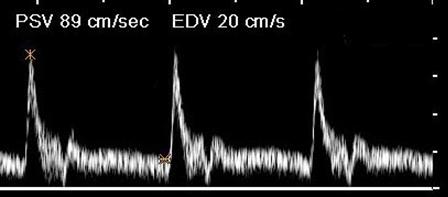

Where is the waveform?

CCA